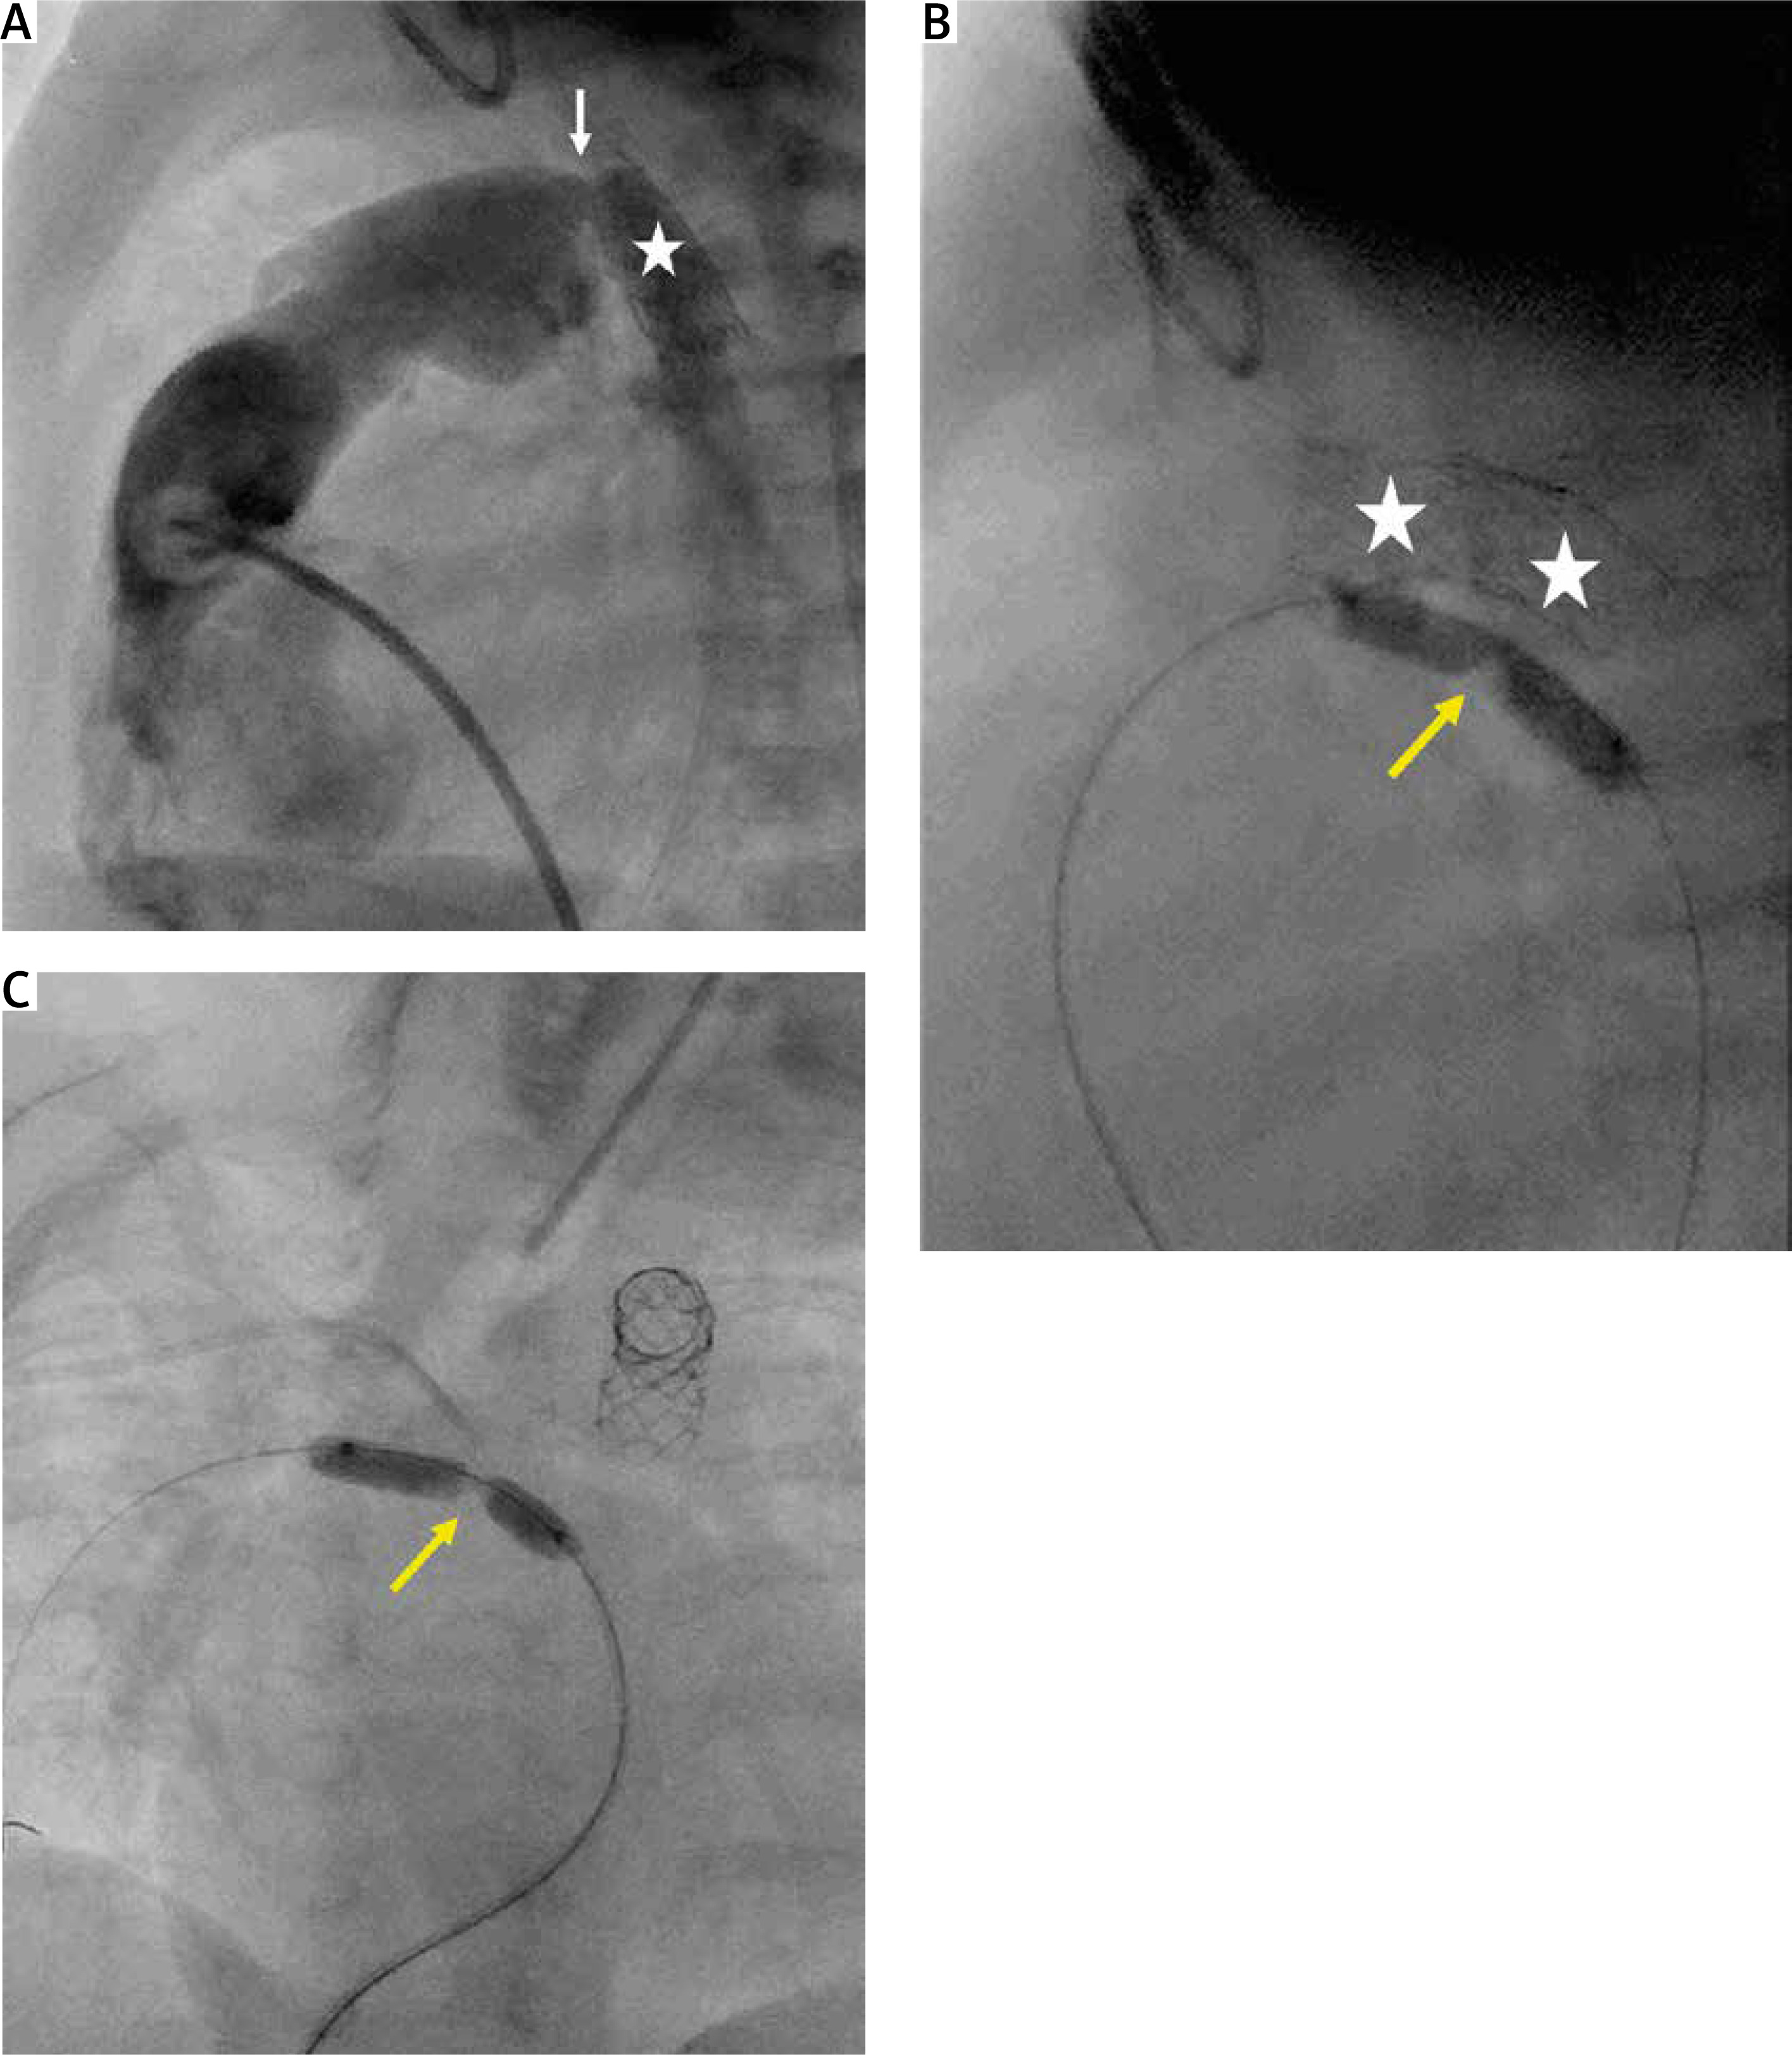

Figure 4

Arterial duct stent implantation during hybrid procedure. A – Pulmonary artery angiography during hybrid procedure performed through the sheath introduced into the artery. Tight bands over the pulmonary branches (yellow arrow). Wide arterial duct (white star). B – A stent Palmaz Genesis 8 mm/12 mm (white arrow) implanted into the proximal part of the arterial duct. Distal arterial duct stenosis (red arrow). C – Arterial duct angiography following second Palmaz Genesis 8 mm/12 mm stent deployment (dash line) and wide antegrade flow into the descending aorta and obstructed retrograde flow into the aortic arch through the stenotic isthmus (white arrow)